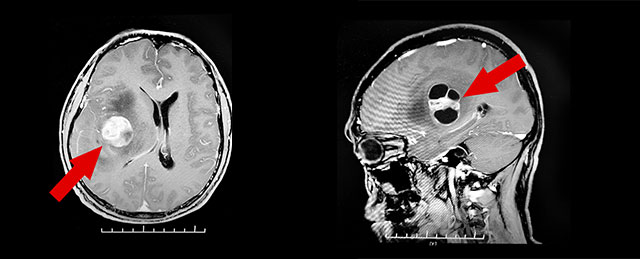

PET/CT檢查,結(jié)果顯示:右側(cè)額頂葉島葉見團片混合密度灶。頭顱增強磁共振檢查發(fā)現(xiàn),右側(cè)顳島葉團塊狀囊實樣占位,病灶大小約2.9*2.5*3.9cm,毗鄰右側(cè)側(cè)腦室及第三腦室受壓變窄、左側(cè)偏移。結(jié)合病灶影像特點,考慮為膠質(zhì)瘤可能性大。

▲右側(cè)顳島葉團塊狀囊實樣占位